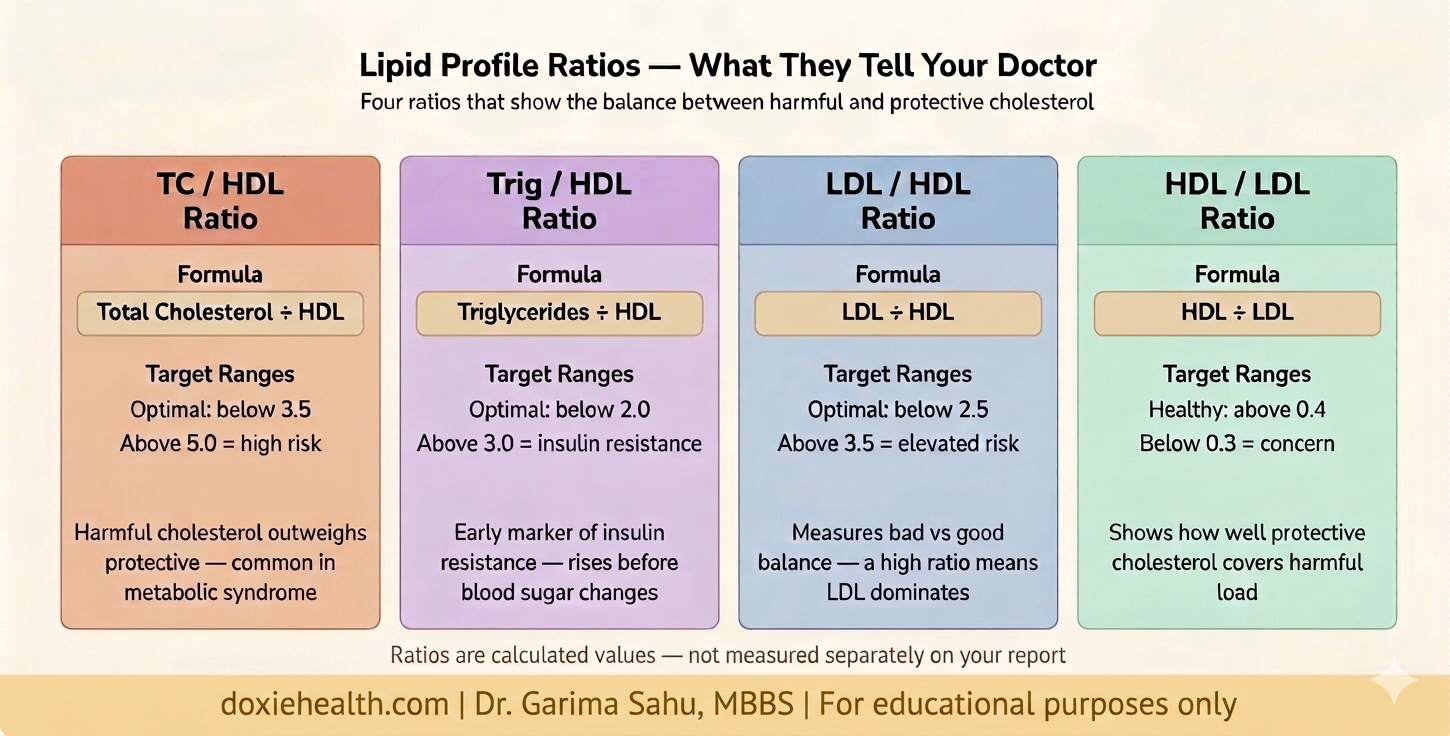

The Ratios — What They Add

Your lipid report includes four ratios. They are not independent markers — they are mathematical relationships between existing values. However, they give a quick snapshot of the balance between harmful and protective cholesterol.

Key Clinical Insights

- Never read total cholesterol alone — always look at LDL, HDL and triglycerides together as a pattern

- Low HDL is as important as high LDL — an HDL below 40 mg/dL is an independent risk factor for heart disease

- The Trig/HDL ratio is an underused early marker — a ratio above 3.0 suggests insulin resistance before glucose levels become abnormal

- LDL — Direct is more accurate than calculated LDL — particularly when triglycerides are elevated above 200 mg/dL

- TC/HDL ratio above 5.0 — suggests significant cardiovascular risk

- Trig/HDL ratio above 3.0 — early marker of insulin resistance worth investigating

Your lipid profile is a window into your long-term cardiovascular and metabolic health. Each marker tells a specific part of the story — and no single number gives the full picture.

LDL drives plaque build-up. HDL clears it. Triglycerides reflect your metabolic health. The ratios tell you how these markers relate to each other.